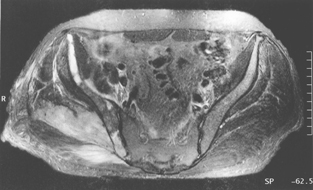

Radiography of his hips, pelvis and lumbosacral spine revealed mild degenerative changes only. A bone scan showed increased uptake in the region of the right buttock, right sacroiliac joint and the superior aspect of the right acetabulum. Computed tomography (CT) scan revealed diffuse swelling involving the right gluteus medius and piriformis muscles (Box, Figure 1). Magnetic resonance imaging (Box, Figure 2) confirmed these findings, but also showed swelling of the obturator internus and part of the gluteus maximus muscles, as well as some increased signal in the right iliac bone seen on T1-weighted images.